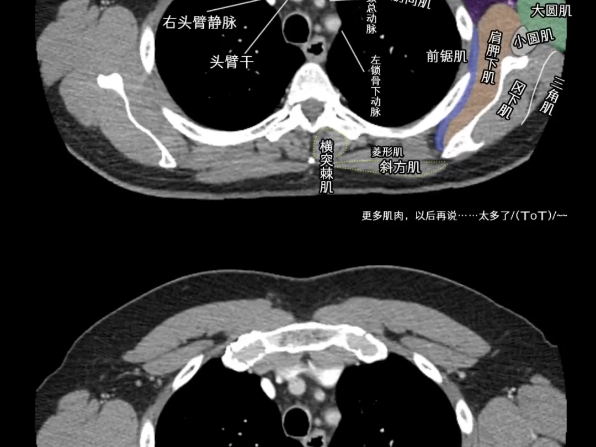

胸部ct解剖有意识地学习基础结构—适合零基础入门胸部ct解剖结构的教程,每一帧学习都有收获!